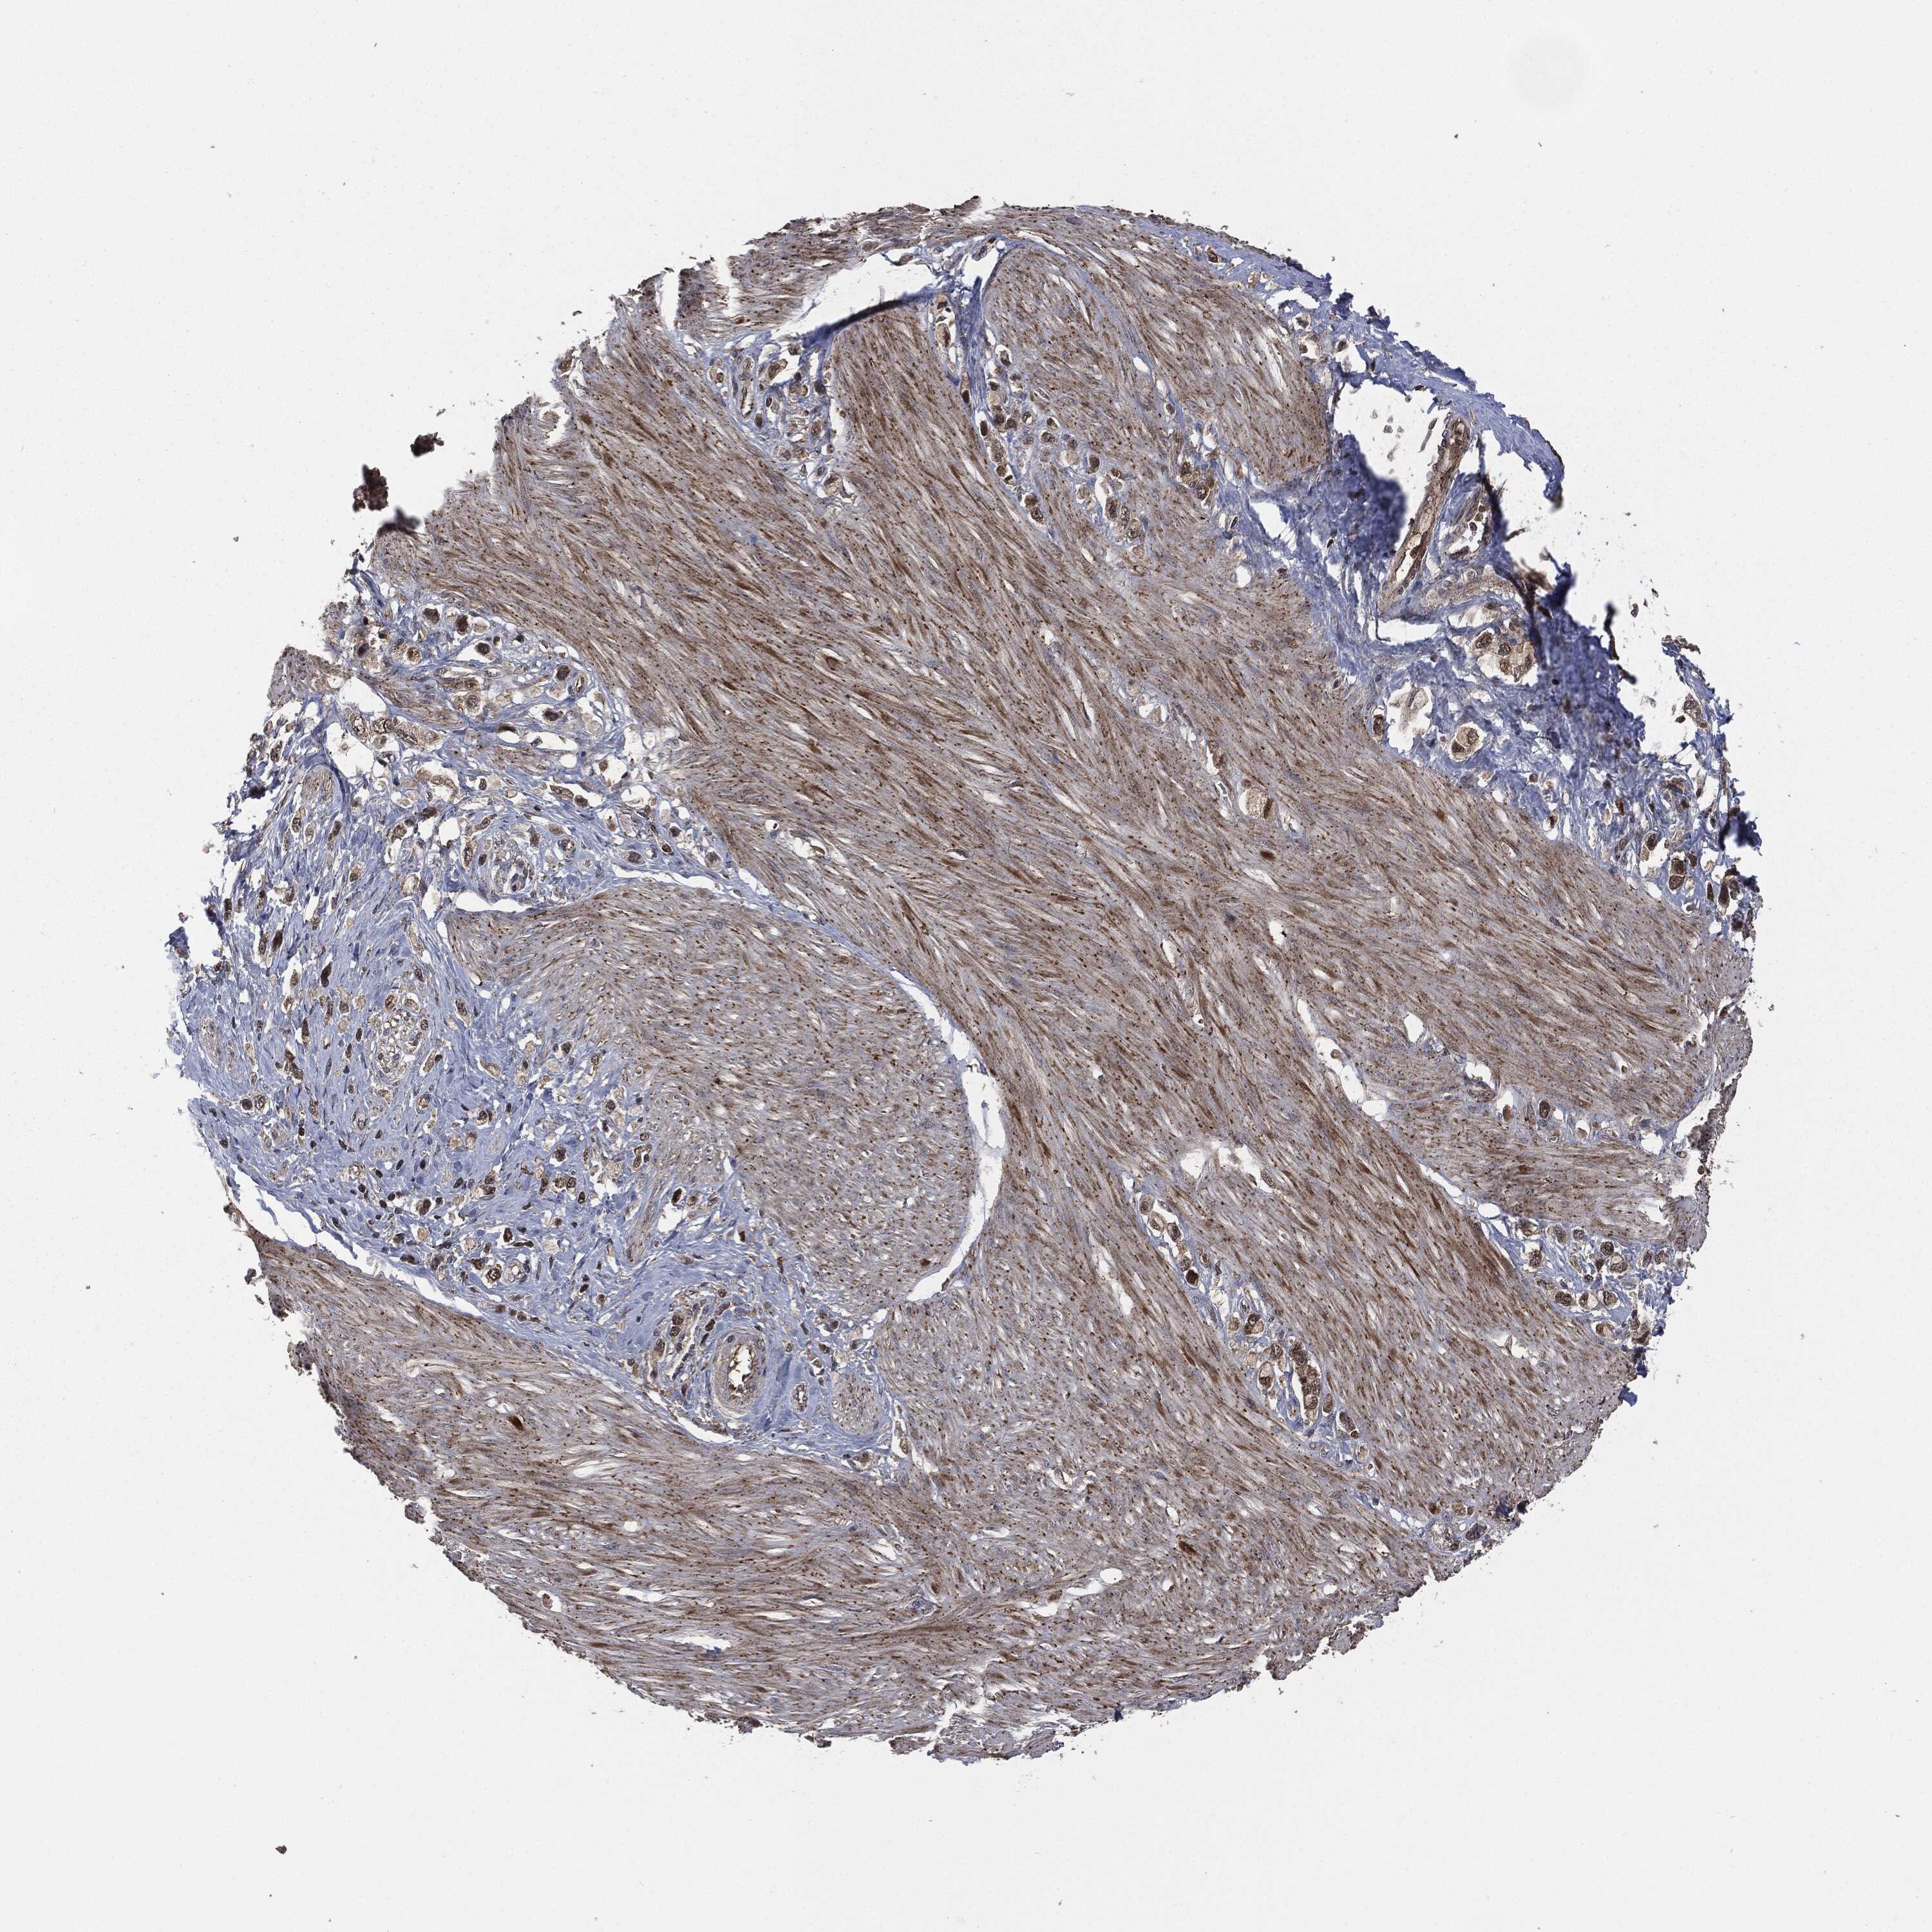

STOMACH CANCER - Protein expressioni

A mouse-over function shows sample information and annotation data. Click on an image to view it in a full screen mode. Samples can be filtered based on level of antibody staining by selecting one or several of the following categories: high, medium, low and not detected. The assay and annotation is described here.

Note that samples used for immunohistochemistry by the Human Protein Atlas do not correspond to samples in the TCGA dataset.

Antibody stainingi

Antibody staining in the annotated cell types in the current human tissue is reported as not detected, low, medium, or high, based on conventional immunohistochemistry profiling in selected tissues. This score is based on the combination of the staining intensity and fraction of stained cells.

Each image is clickable and will lead to virtual microscopy that enables deeper exploration of all samples and also displays staining intensity scores, fraction scores and subcellular localization as well as patient and tissue information for each sample.

HPA049830

CAB002015

CAB080330

CAB080331

CAB080332

Staining

High

Medium

Low

Not detected

Intensity

Strong

Moderate

Weak

Negative

Quantity

>75%

75%-25%

<25%

None

Location

Nuclear

Cytoplasmic/membranous

Cytoplasmic/membranous,nuclear

Adenocarcinoma, NOS

Adenocarcinoma, High grade